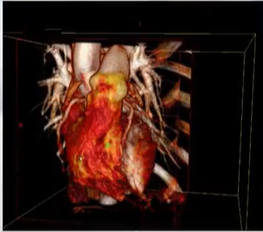

生活中是二维的,医学上通常还有3维和4维的。比如在关注心脏跳动的时候,不仅关注其三维结构,还要关注时间轴变化。

三维图像:一个像素描述成一个体素。

(2)三维图像:被描述成f(i,j,k)

三维图像:除了raw data之外,还有info,vox,mnc,dicom。医学图像中常用的是dicom

(2)三维:

如下激光的扫描图像,它是二维扫描仪进行了三维描述,用激光沿着人体进行三维扫描,这样能采集到人体三维的表面结构,进而绘制三维人体。

后续还需要对图像进行三维绘制,建模,表达,作为输出展示给用户。

(6)三维超声